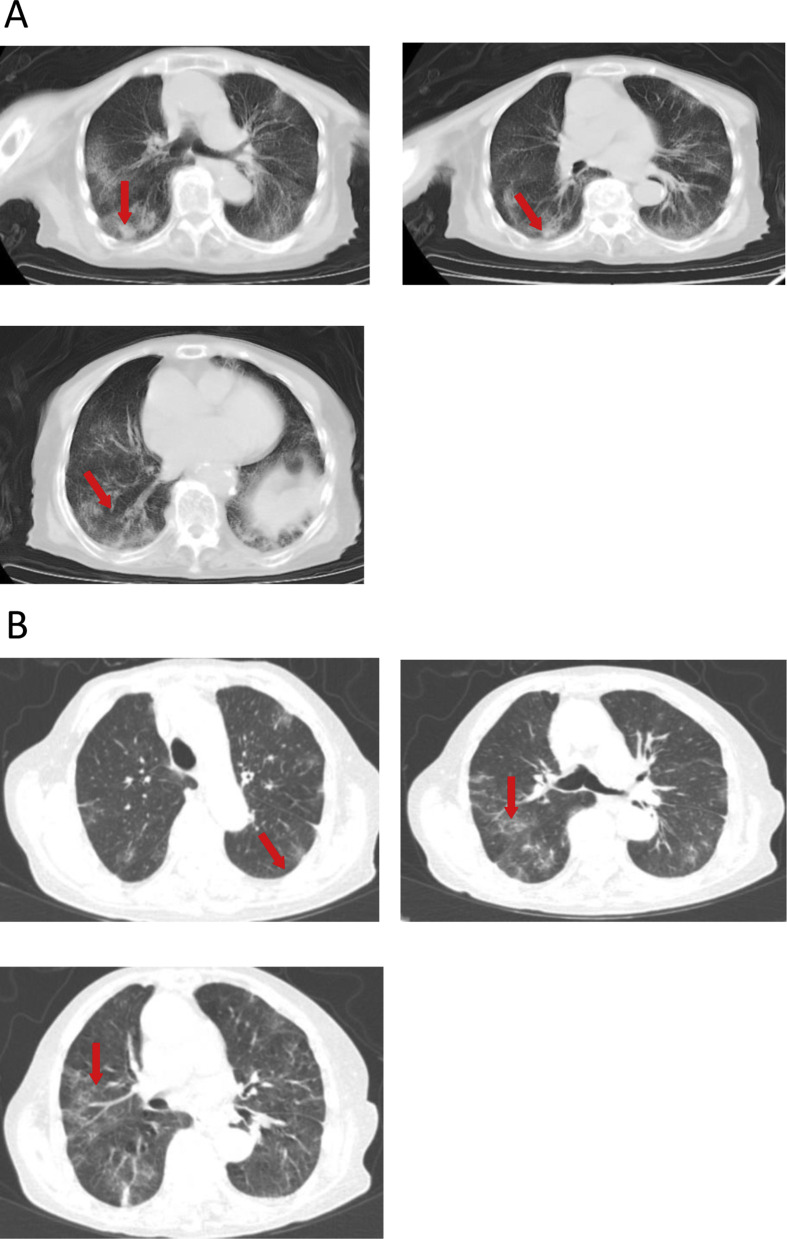

Admission examined showed a temperature of 36.9 °C, a pulse of 80/min, a respiratory rate of 22 min, and a blood pressure of 126/66 mmHg (Table 1). Bilateral lung sounds were coarse upon auscultation. No other remarkable abnormalities were observed. Routine blood test showed a reduction in WBCs (1.77 × 109/L), lymphocytes (0.34 × 109/L) and neutrophils (1.18 × 109/L) and a decrease in IgG levels (9.8 g/L). Blood gas analysis showed elevated pH (7.6), reduced PaO2 (58 mmHg) and decreased HCO3 - (20.6 mmol/L) (Table 3 ). Admission chest CT scan revealed multiple bilateral ground glass opacities and mainly peripheral exudative changes (Fig. 3 A).

Figure 3.

(A) Chest CT scan on February 16, 2020 of an 82-year old female patient referred with a confirmed diagnosis of COVID-19 for 5 days shows multiple bilateral ground glass opacities and mainly peripheral exudative changes. (B) Chest CT scan on February 23, 2020 reveals multiple bilateral ground glass opacities and scant cord-like shadows, which are mainly peripheral.

The patient received recombinant interferon α aerosol (500 × 106 U twice daily), intravenous methylprednisolone (40 mg twice daily), intravenous esomeprazole (40 mg twice daily), and oral umifenovir (0.2 g, three times daily). Laboratory study on February 19, 2020 revealed lymphocytes at 0.34 × 109/L, increased proBNP (1219 pg/mL), decreased aPPT (24.2 s, normal references 26.5–39.3 s), increased D-dimers (280 ng/mL) and FDP (3.13 μg/L). The patient was given oxygen supplementation (4 L/min) to correct hypoxemia on February 19, 2020 and human immunoglobulin (10 g/day) for 6 days. Plasma glucose control was managed by consultation with endocrinologists at the hospital and chronic bronchitis was treated by pulmonologists. Nutritional support and traditional Chinese medicine were also provided. The patient showed improvement and chest CT scan on February 23, 2020 showed multiple bilateral ground glass opacities and scant cord-like shadows, which were mainly peripheral (Fig. 3B). The patient was discharged from the hospital on March 12, 2020.